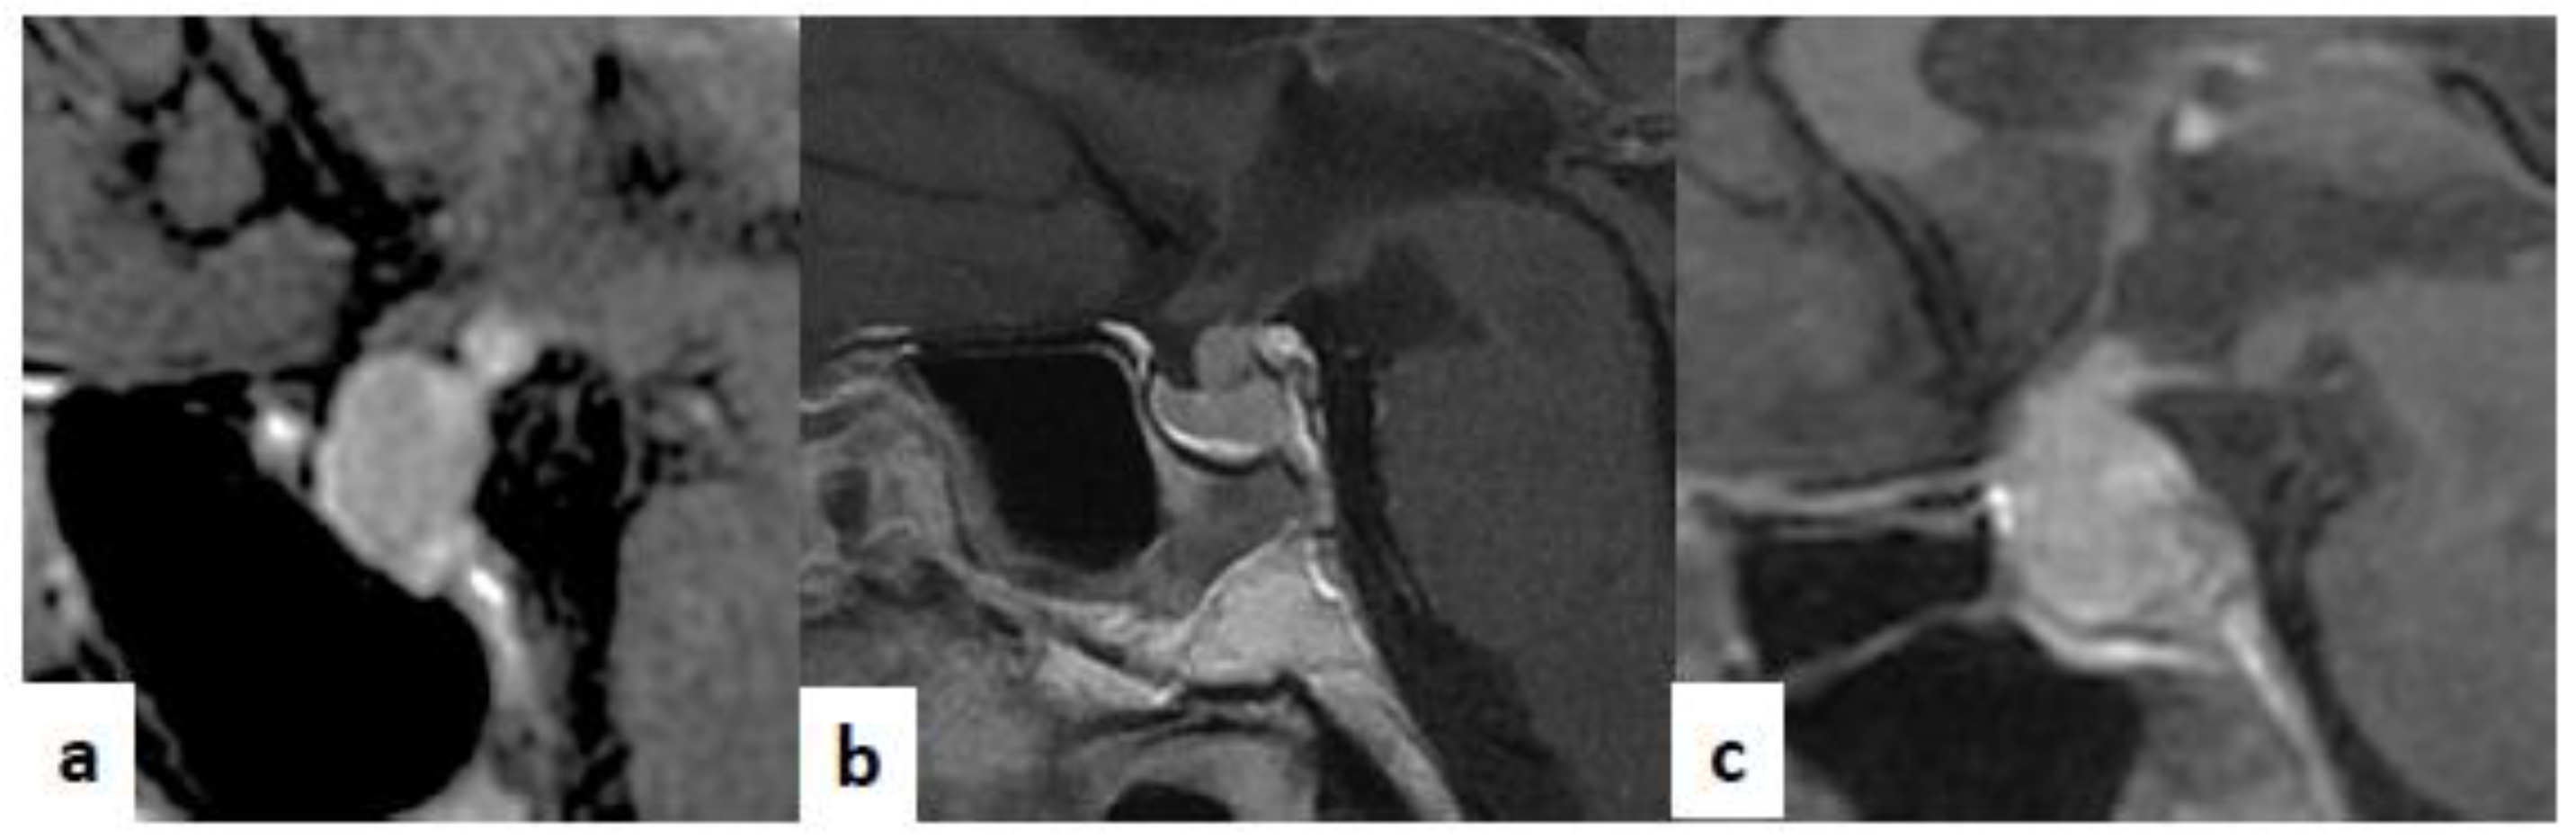

Figure 3.

Sagittal T1-weighted (T1-w) images after contrast medium injection. (a) A case of adeno-hypophysitis. The adeno-pituitary and the pituitary stalk are swollen. The hyper-intense signal of the neuro-pituitary is normally present on the T1-w image. (b) A case of infundibulo-neuro-hypophysitis. The pituitary gland is reduced in size. The pituitary stalk is swollen. The hyper-intense signal of the neuro-pituitary is lost on the T1-w image. (c): A case of pan-hypophysitis. The pituitary gland and stalk are swollen. The hyper-intense signal of the neuro-pituitary is lost on the on T1-w image.